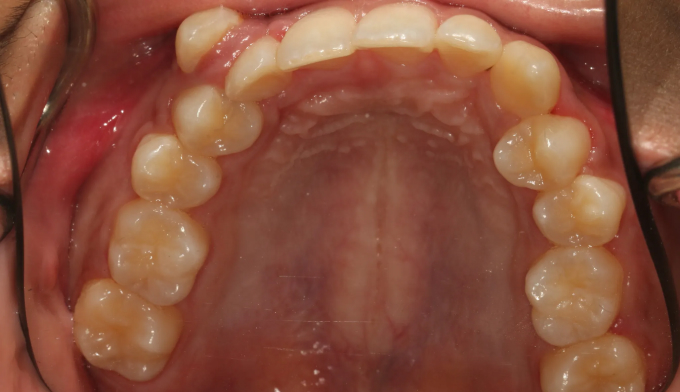

덧니가 심한 학생들, 특히 중,고등학생들을 보면 안타까울때가 종종 있습니다.

조금 더 이른나이에 교정을 시작하였더라면 무리하게 발치하지 않고도 충분히 치아를 가지런하게 할 수 있었을 텐데 라는 생각을 지울수가 없습니다.

이번 케이스도 뒤늦게 송곳니가 덧니로 나오는것을 확인하고 치아교정을 하고자 내원한 중학생입니다.

부족한 공간이 꽤 많고, 입도 돌출되어 보여서 어쩔수 없이 발치교정을 계획하였습니다.

총 치료기간은 23개월입니다.